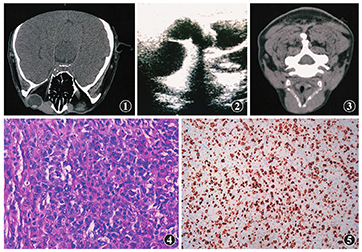

泪囊髓外浆细胞瘤一例论文

泪囊区弥漫大b细胞淋巴瘤一例